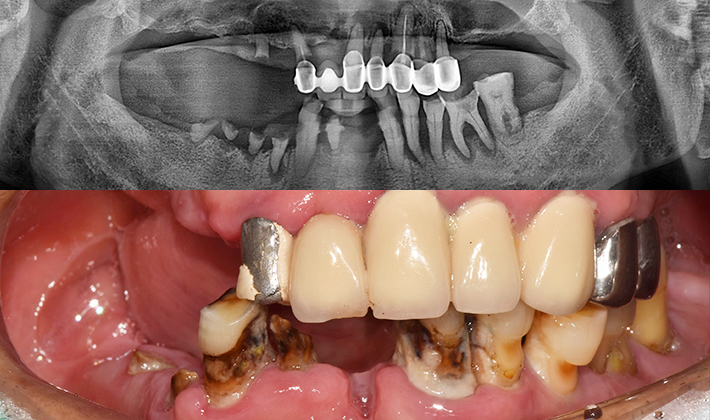

before

after

※ 위 임상사진은 동일조건으로 촬영되었으며, 사진에 대한 별도의 조작이 처리되지 않았습니다.

※ 위 임상사진 및 포트레이트는 환자와의 포괄적인 초상권 계약 이후 사용하고 있습니다.

※ 수술 및 치료과정에서 부작용이 발생할 수 있으므로 충분한 상담과 신중한 판단이 요구됩니다.

실제 치료 사례

수많은 환자들이 고민 끝에 선택한 치료,

그리고 그 후의 놀라운 변화

- ※ 위 임상사진은 365서울원탑치과에서 진료를 시작하고 마친 동일한 환자의 사진입니다.

- ※ 위 임상사진은 동일한 장소에서 동일한 조건으로 촬영되었으며, 사진에 대한 별도의 조작이 처리되지 않았습니다.

- ※ 수술 및 치료 과정에서 부작용이 발생할 수 있으므로 의료진과의 충분한 상담과 신중한 판단이 요구됩니다.